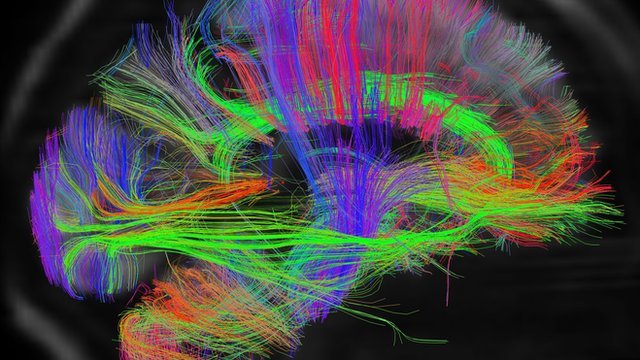

Usando una técnica llamada imagen por resonancia magnética funcional, los neurocientíficos pueden poner a alguien en un escáner y ver qué partes del cerebro se activan cuando hacen o piensan en algo.

Una simple acción, como cerrar y abrir el puño de la mano o decir unas pocas palabras requiere de la actividad de mucho más de una décima parte del cerebro. Incluso cuando se supone que no se está haciendo nada, el cerebro está haciendo mucho, ya sea controlando funciones como respirar y el palpitar del corazón, o recordando cosas por hacer. (1)

Incluso al dormir, el cerebro se mantiene activo, como muestra esta imagen de la actividad al soñar.

Incluso al dormir, el cerebro se mantiene activo, como muestra esta imagen de la actividad al soñar.